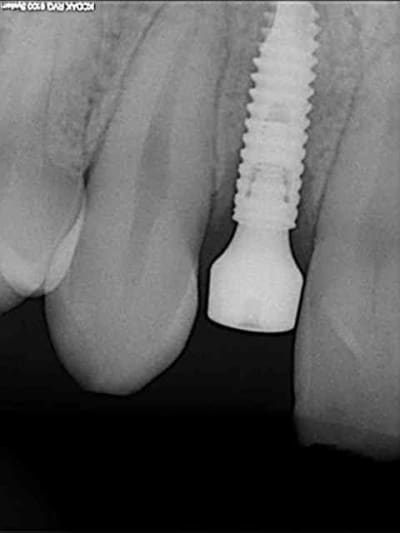

tes implants 12 et 13 n'ont pas le même niveau d'enfouissement, tu n'as pas peur d'une lyse osseuse de 13 pour venir au niveau du col de 12 ?

01/09/2010 à 16h54

-1 ou 2 mois plus tard ( je sais plus)

- empreinte avec transfert pop in

- pilier zircone esthétique Axiom

- prothèse et pilier

- pilier zircone en place

- couronne en place (petite compression gingivale)

fin du traitement